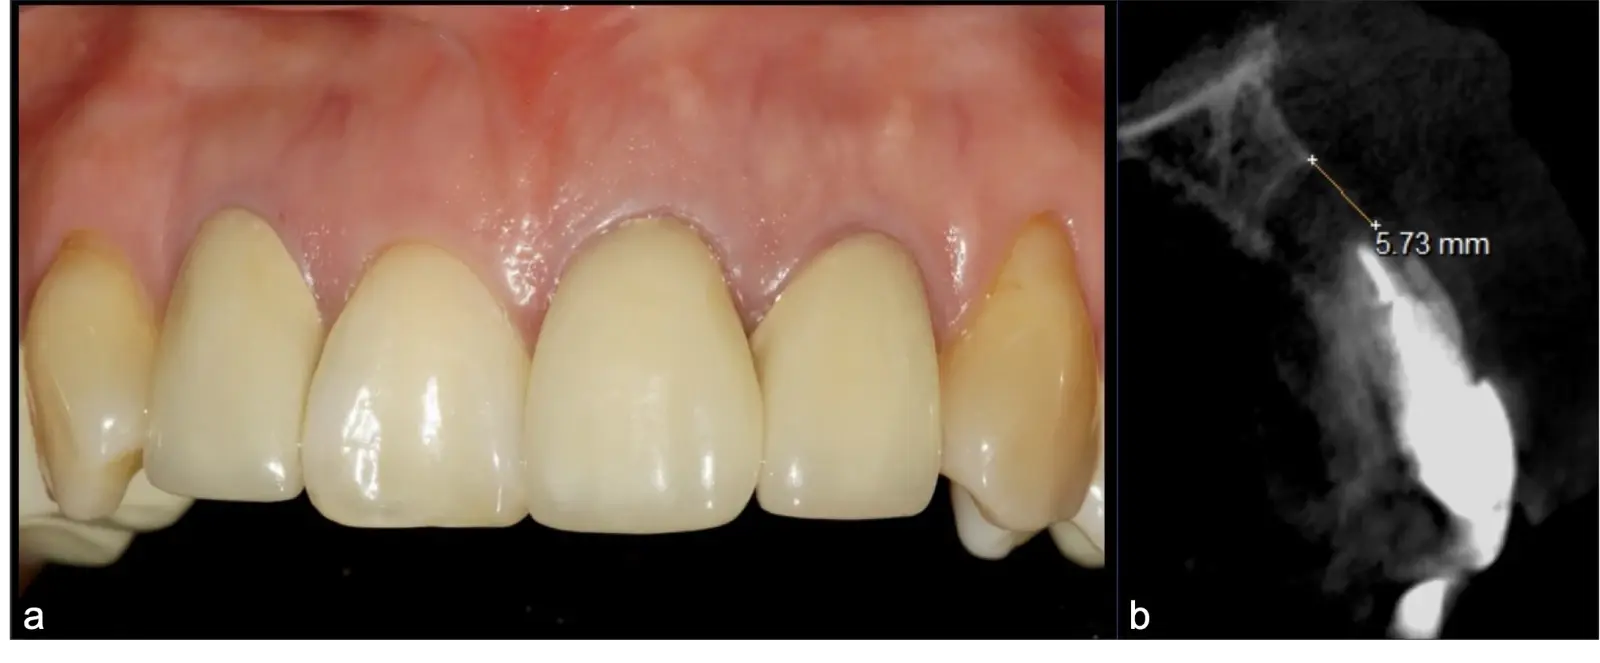

La microcirugía endodóntica apical busca conservar la mayor cantidad de longitud de raíz y de hueso circundante sano para no afectar la estabilidad de la pieza.11 Por ello, es ideal el uso de microscopios, elementos de magnificación, instrumental específico (insertos de ultrasonido endodónticos) y materiales de sellado eficientes para el tratamiento retrogrado. Su éxito es alto y evidencia una cicatrización ósea completa en el 74% de los casos al año de tratamiento.12 Cabe destacar que este logro está asociado también, a predictores propios de cada paciente, como la edad, tipo de pieza, profundidad de sondaje y extensión de la lesión.1 El uso complementario de la tomografía computarizada es resaltante como el instrumento imagenológico de elección para la etapa de planificación microquirúrgica,13 ya sea para una ejecución a mano alzada o con guías prefabricadas.14,15

Una vez limpia la zona apical, se corrobora la integridad de la raíz y se evalúa el grado de extensión de la lesión. Si el defecto óseo es pequeño, se procede a realizar la preparación del conducto y obturación retrógrada de ser el caso. Si el defecto óseo es de gran tamaño e inaccesible a los insertos, se procede a realizar un corte de por lo menos 3 mm de ápice radicular conteniendo los posibles conductos aún infectados11 empleando habitualmente insertos de borde aserrado con/sin marcas de medición para un trabajo seguro7 (Figura 7).